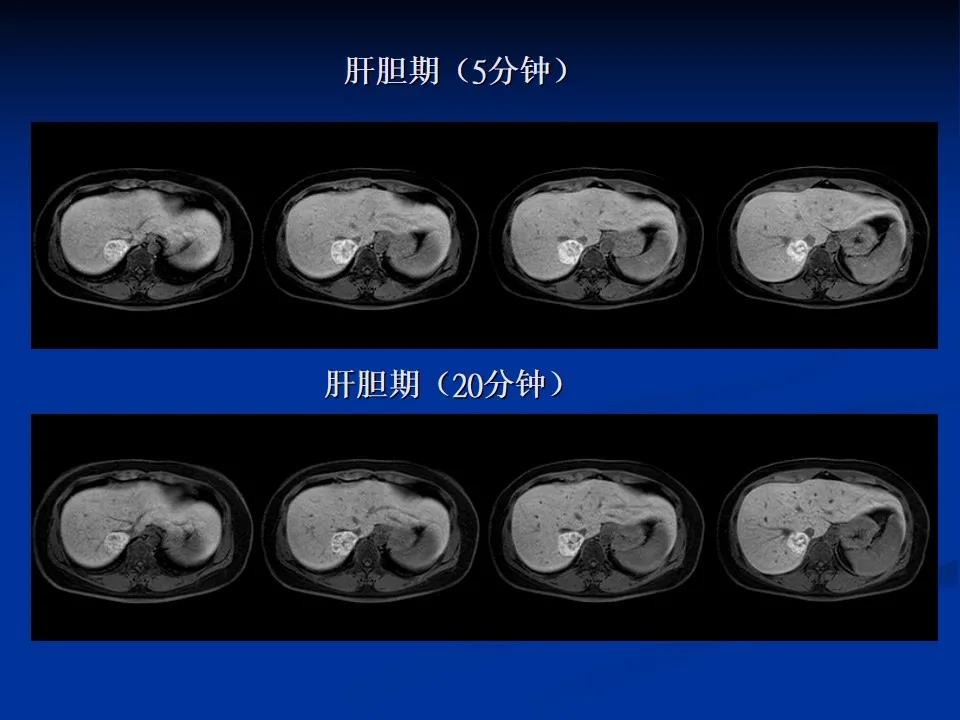

扫描后诊断意见为肝右叶后上段富血供肿块(瘤体以含肝正常细胞、纤维组织为主),病灶紧贴肝右静脉、下腔静脉,考虑肝局灶性增生结节(FNH),建议定期复查。

他指出,肝局灶性增生结节由正常肝细胞、胆管、畸形血管错构的肝良性肿瘤性病变,无恶变倾向及并发症少见,大部分不需要治疗,其鉴别诊断为肝腺瘤(有恶变倾向,需要治疗)、肝血管瘤(少恶变但有增长趋势及并发症)、肝癌(恶性、需急切治疗)。上述病变常规的检查如超声、CT及磁共振平扫+增强检查,影像医生多凭影像病理改变及经验判断而诊断,诊断及鉴别诊断难度较大及不确定较多,而误诊率也相对较高,肝特异性对比剂从分子影像学的角度能很好的解决诊断问题,肝病变是否含有正常肝的枯否细胞(枯否细胞对钆塞酸二钠特异性吸收)(肝胆期)、肿瘤的血供(多期动态)结合CT及常规磁共振序列,极大提高诊断精确率,减少误诊率,真正做到精准诊断、精准医疗。